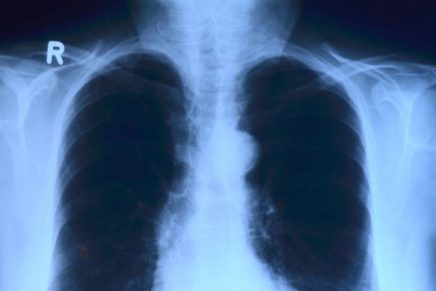

CC toubibe - Pixabay

Inteligencia artificial ahora detectaría el cáncer del pulmón

Un grupo de Científicos de Google y de la Universidad de Northwestern han creado un sistema de inteligencia artificial capaz de detectar  el cáncer de pulmón, con una afectividad mucho mayor a la de los radiólogos, lo que podría favorecer el diagnóstico temprano de un tumor que al año mata a más de un millón de personas en el mundo.

Basándose en esto, los científicos estadounidenses desarrollaron un algoritmo capaz de detectar nódulos pulmonares malignos, a veces minúsculos, a partir de resultados de un TAC -tomografía axial computarizada- del tórax, con un empeño y precisión igual o mejor que el de los radiólogos.

Para ello, “entrenaron” al sistema en 42.290 imágenes de tomografía computarizada y encontraron que el sistema de inteligencia artificial fue capaz de detectar los módulos con una precisión del 94% en 6.716 casos de prueba.

El modelo se comparó con las pruebas hechas por seis radiólogos tanto cuando estos disponían de imágenes por TAC previas como cuando no, y en los dos casos la máquina superó a los radiólogos expertos.

Además, el sistema de aprendizaje profundo también produjo menos falsos positivos y menos falsos negativos de tumores, afirman los científicos en una nota de prensa de la universidad estadounidense.

Mozziyar Etemadi, profesor de Medicina y de Ingeniería en Northwestern y uno de los autores de este artículo, explica que los radiólogos generalmente examinan cientos de imágenes bidimensionales en una sola tomografía computarizada, pero este nuevo sistema permite analizar instantáneas en 3D.

“La inteligencia artificial en 3D puede ser mucho más sensible en su capacidad de detectar el cáncer de pulmón temprano que el ojo humano que mira imágenes en dos dimensiones”, resume este investigador.